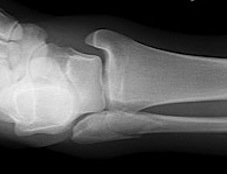

Isolated Weber C fracture

Weber C fracture Weber C fracture with deltoid ligament injury

Maisonneuve injury: proximal fibula with open medial clear space

Definition

Fracture above syndesmosis

Syndesmosis disrupted +/- deltoid ligament

Syndesmotic injury